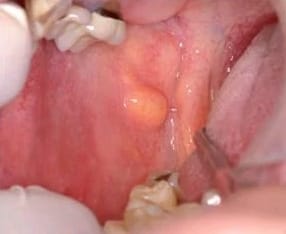

Alguien sabe lo que es?Son como dos bolitas en la parte interior de las mejillas

Hace un día que no puedo comer porque los bultos chocan con los dientes y me da un dolor insoportable, ya no soporto el dolor porque además me duele la mandíbula y me duele la cabeza, siento que me quiero morir?